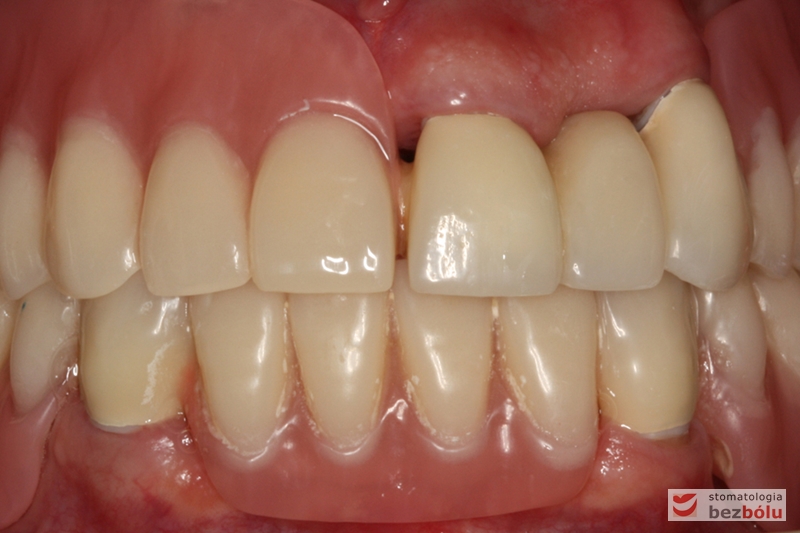

Efekt końcowy leczenia protetycznego